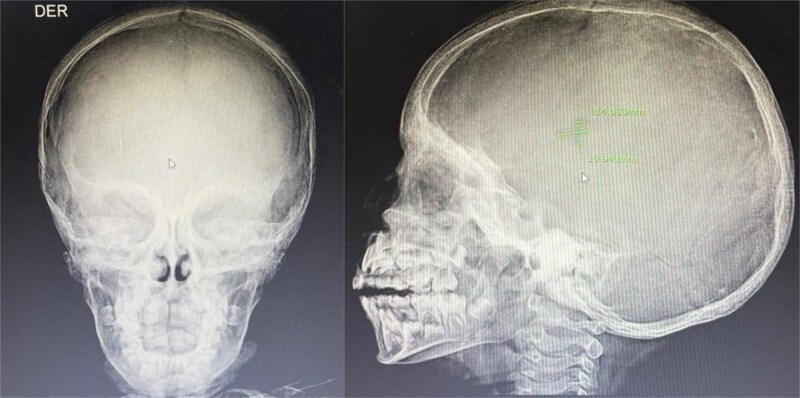

朗格汉斯细胞组织细胞增生症(LCH)是一种罕见的疾病,朗格汉斯细胞浸润到各种器官,导致组织损伤。本病例描述一名确诊为LCH的6岁男性,其表现为疲劳、过度口渴、多尿和不明原因的体重增加等症状恶化。x线检查显示颅骨和长骨有广泛的溶骨性病变,符合LCH。此外,通过激素检测和影像学证实,患者出现明显的内分泌功能障碍,包括甲状腺功能减退、尿崩症和肾上腺功能不全。该病例强调了在LCH患者中考虑内分泌功能障碍的重要性,并强调了多学科方法在管理复杂病例中的作用。激素替代治疗,以及LCH的化疗开始,患者表现出临床改善。

Langerhans cell histiocytosis (LCH) is a rare disorder in which Langerhans cells infiltrate various organs, causing damage to tissues. This case describes a 6-year-old male diagnosed with LCH, who presented with worsening symptoms of fatigue, excessive thirst, polyuria, and unexplained weight gain. Radiographic findings revealed extensive osteolytic lesions in the skull and long bones, consistent with LCH. Additionally, the patient developed significant endocrine dysfunction, including hypothyroidism, diabetes insipidus, and adrenal insufficiency, as confirmed through hormonal assays and imaging. The case emphasizes the importance of considering endocrine dysfunction in patients with LCH and underscores the role of a multidisciplinary approach in managing complex cases. Hormonal replacement therapy, along with chemotherapy for LCH, was initiated, and the patient showed clinical improvement.